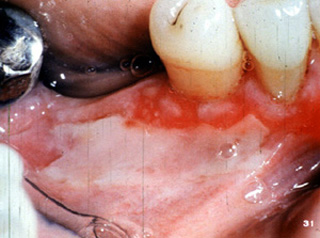

El penfigoide benigno tiene una marcada tendencia a involucrar la encía marginal. La descripción clínica a menudo usada para estas lesiones es "gingivitis descamativa" Debe señalarse que ésta es sólo una descripción clínica y no un diagnóstico definitivo. En la encía  tiene una marcada apariencia eritematosa.

Aquí hay otro paciente con la encía afectada por la enfermedada..

Aquí hay  áreas de ulceración y descamación gingival.